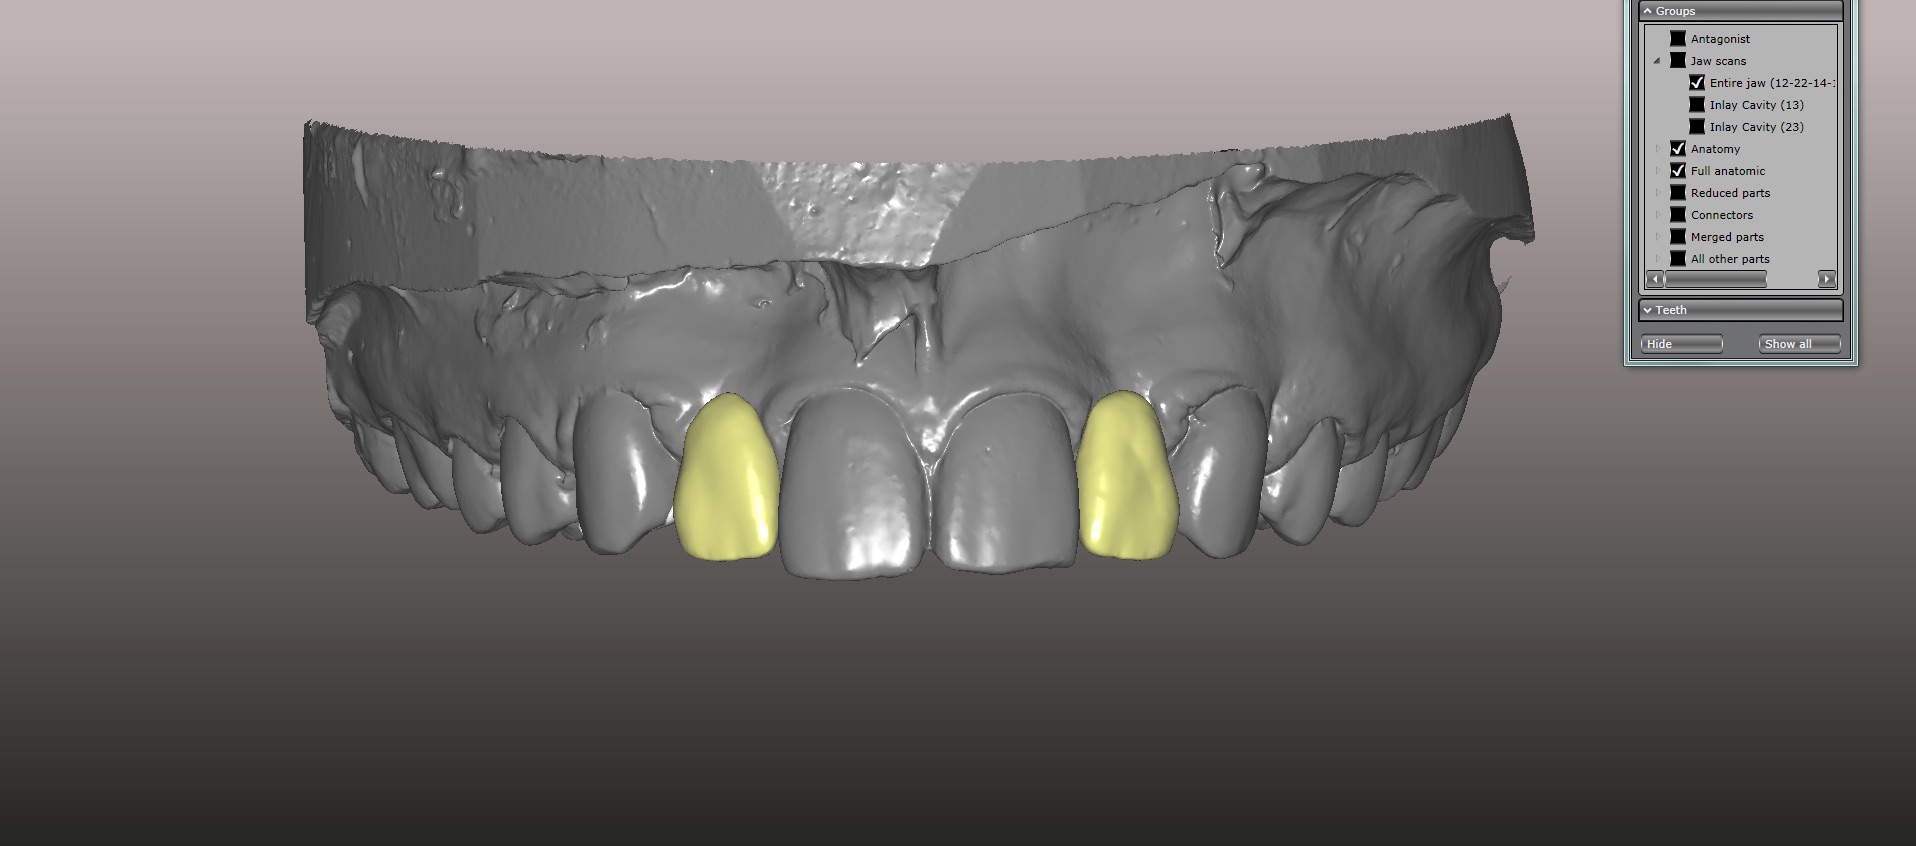

An approach utilizing CAD/CAM was employed to fabricate an accurate fitting, retentive, and esthetic ceramic single-wing resin-bonded bridge. Impressions were taken of the patient and scanned in the laboratory using maximum intensity projection. The scanned models were then used to design the final prosthetic frames utilizing EXOCAD software. The retainer positions and extensions were designed on the models based on the occlusal clearance (Figure 15). Next, the replacement tooth forms were chosen from a virtual library (Figure 16), and try-in PMMA bridge prototypes were milled in Primotec USA PMMA. This allowed for try-in of the design, adjustment of the contacts, and intraoral evaluation of the ridge contact (Figure 17). Once tried and idealized for both fit and occlusion, the design was sent back to the lab to rescan. Utilizing the software, a cut back was made on the lateral incisor (Figure 18), and a 0.3mm space was also virtually designed on the internal surface of the retainer wing to allow layering with feldspathic ceramic (Figure 19). The 0.2 mm internal edge of the wing was designed to be left intact to allow for precise seating and verification of fit on the model. After the frame was milled in zirconia (Zirconzahn, Prettau), it was verified on the model, and high fusing margin porcelain (Noritake CZR) was mixed with a clear utility wax and applied to the internal 0.3 mm depression. This was baked in the oven at a high temperature, allowing the wax to burn out and leaving the feldspathic ceramic fused to the internal surface of the retainer. Once cooled, this was checked for precise fitting on the model and adjustments were made to ensure full seating.

(15.) Models mounted in maximum intensity projection, allowing design of the retainer extensions on the lingual of the canines (in pink).

Figure 15

(16.) Virtual design of anatomic form generated from a virtual library of tooth forms, which was used to fabricate temporary PMMA resin-bonded bridges.

Figure 16